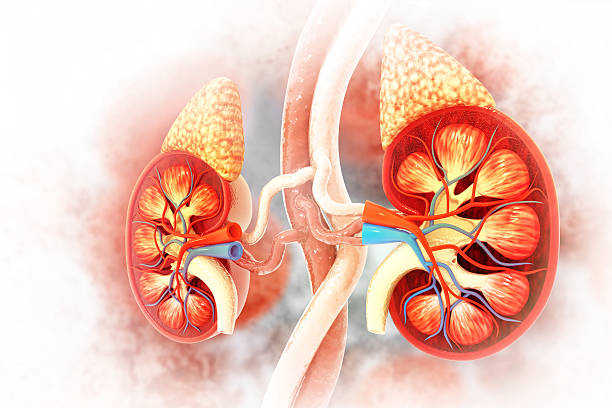

Kidneys are metabolically active organs. They process toxins, regulate pH, balance electrolytes, and manage waste — all while being exposed to oxidative stress every single day. This makes them especially vulnerable to free radical damage, inflammation, and gradual cellular breakdown.

Among these nutrients, antioxidants play a central role. Oxidative stress accelerates kidney decline by damaging nephrons (the kidney’s filtering units). Antioxidants neutralize free radicals before they harm kidney cells.

Kidney cells are constantly exposed to oxidative byproducts from filtration and metabolism. Over time, this leads to cellular injury, inflammation, and scarring, which reduces kidney efficiency and accelerates disease progression.

The kidneys operate under constant metabolic stress due to their continuous role in filtering blood, regulating fluid balance, and removing waste products, which exposes them to high levels of oxidative byproducts that can damage cellular structures over time.

The kidneys filter nearly 180 liters of blood daily. That means they are constantly exposed to metabolic waste, environmental toxins, medications, heavy metals, and oxidative byproducts. This filtration workload creates chronic oxidative stress, which gradually damages kidney tissues.